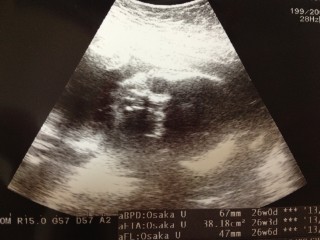

写真:26w1d:やんさん:目が開いてて!

26w1dのエコーです(°▽°) 性別は 女の子かな?っと言われてますが、まだ確定ではないです(..) 目が開いてて、おもわず「怖っ!」って言ってしまいました~!笑 次から二週間に一度の検診になったので楽しみです。